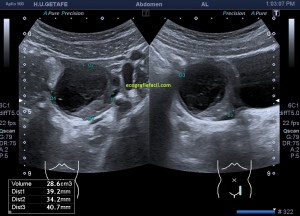

Durante la exploración de una eco de abdomen en el contexto de un paciente que acude por elevación de transaminasas observo una imagen heterogénea, irregular, con una pared marcadamente calcificada, bilobulada de gran tamaño que medí en dos partes ya que me pareció claramente que estaban diferenciadas.

Una de ellas, la primera, era mucho más hiperecogénica y más pequeña, su centro estaba mas calcificado, su sombra acústica posterior era mucho más acuciada y llamaba más la atención. Justo al lado, otra lesión de mayor tamaño, su calcificación era mucho más sutil y más periférica delimitando una LOE hipoecogénica de un tamaño muy importante, adyacente a la más pequeña, como he comentado previamente. Ambas sin señal Doppler.